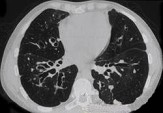

- 单项选择题男,18岁, 咳嗽,咳痰, 咯血半月余,CT如图.选出最可能的诊断 ( )

A、过敏性肺炎

B、支气管扩张

C、原发性肺结核

D、大叶性肺炎

E、肺癌